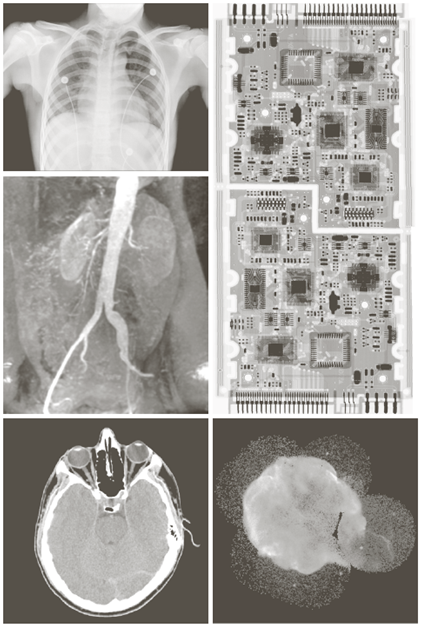

X-ray image

• X선의 투과성을 이용

Image

Ultraviolet image

• 주요 응용분야: 석판인쇄, 산업용 검사, 형광 현미경, 레이저, 생물학 영상, 천문 관측 등

a) 보통옥수수 b) 깜부기병에 걸린 옥수수 c) 백조자리 성운

Visual band and infrared image

• 적외선 영상은 가시광선 영상과 함께 사용되는 경우가 많다

a) 항암제 Taxol b) 콜레스테롤 c) 마이크로프로세서

Visual band image – 영상처리에 의한 품질검사

a) 회로 기판 b) 포장 알약 c) 병 d) 플라스틱 표면의 기포 e) 씨리얼 f) 각막 이식